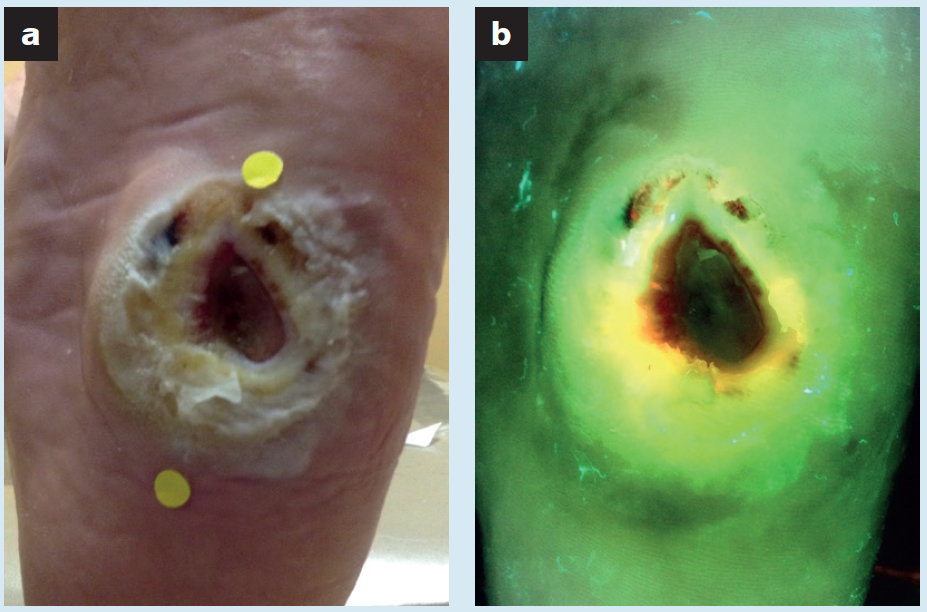

Point-of-care fluorescence imaging reveals extent of bacterial load in diabetic foot ulcers

Armstrong, DG et al. Int Wound J 2023